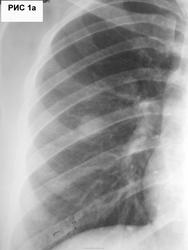

32 года. Экономист. Замужем. Дети 3 и 7 лет. Курит 12 лет. Изменения в S6 правого легкого (рис.1,1а) выявлены при профосмотре. Уехала в командировку. Явилась через 2 мес.Рентгенограмма ОГК (рис.2,2а).

Жалобы на одышку, кашель с мокротой слизистого характера,"упадок сил", температуру 37,5, похудание на 2 кг. Кровь: Hb - 110г/л, лейк.8,9*109/л, палоч. - 13%, лимф.38%, СОЭ - 35 мм/ч. Архива нет.

Нужен правый боковой снимок лёгких.С учётом имееющейся информации, можно предположить инфильтративный туберкулёз с распадом справа в S6 и засевом нижнее поле слева (?) .Дифференцировать с периферическим раком с распадом.

В первую очередь туберкулез. Только непонятно были или нет изменения слева в нижней доле 2 мес. назад.И наверное нужно ТМГ, на снимках внутренний контур полости бугристый.

В "конторе" методом люминесцентной микроскопии обнаружены МБТ. Форма туберкулеза - инфильтративный в фазе распада. С уважением Nikolas